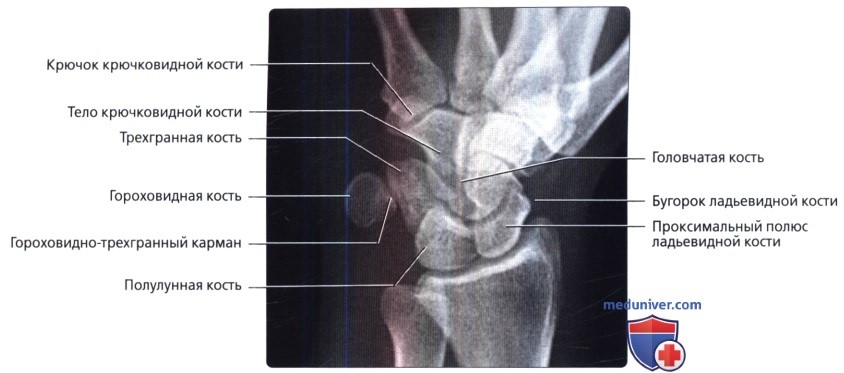

Подборка рентгеновских снимков лучезапястного сустава

Раздел: Объективный взгляд